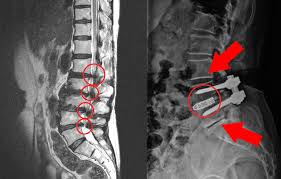

허리협착증은 척추 속 신경이 지나가는 통로인 '척추관'이 좁아지면서, 신경을 눌러 통증이나 저림 등의 증상을 유발하는 질환입니다.

- 요추관협착증은 주로 허리 부분(L3~L5)의 협착으로 인해 발생합니다.

- 퇴행성 변화, 즉 디스크, 인대비후, 관절돌기 비대 등이 원인이 됩니다.